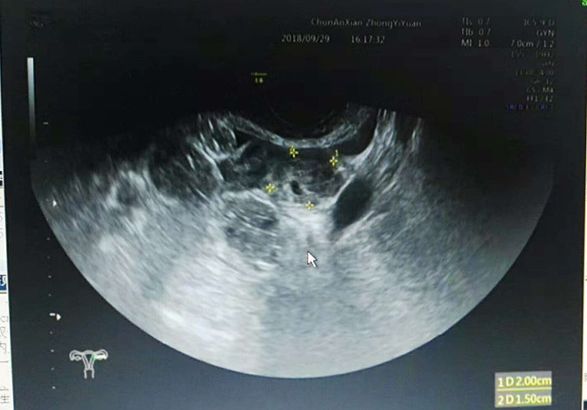

近日,一名38岁女性患者,1个月前在某医院行人流术后出现阴道出血,腹痛,怀疑人流后残留来县中医院妇科门诊就诊。经妇产科仔细检查,结合尿HCG700mIU/ml,超声检查左附件区混合回声团块,最终考虑并非人流后残留,而是存在宫外孕现象,当即给予收住入院。这种宫内孕合并宫外孕的病例非常少见,幸好中医院妇产科临床医生谨慎,超声医生检查仔细,手术及时,一起合作解除了病魔。

复合妊娠是指同时发生在2个或以上种植部位的妊娠,以宫内外复合妊娠常见,在自然妊娠中罕见,发生率约1/30000,随着辅助生殖技术广泛开展,发生率明显增高,达1%左右。宫内外复合妊娠中最常见类型为宫内合并输卵管妊娠约占88.2%,超声是主要诊断方法。

比较好的办法就是做 B 超,B超能够鉴别是正常怀孕还是宫外孕。不过 B 超起码要到怀孕 42 天以后才能做出来,更早一点儿发现的办法是可以抽血化验,检查 HCG,就是测试怀孕的那个指标。如果 HCG 的值隔天能够翻倍的话,那么宫外孕的可能性就很小,基本可以放心了。